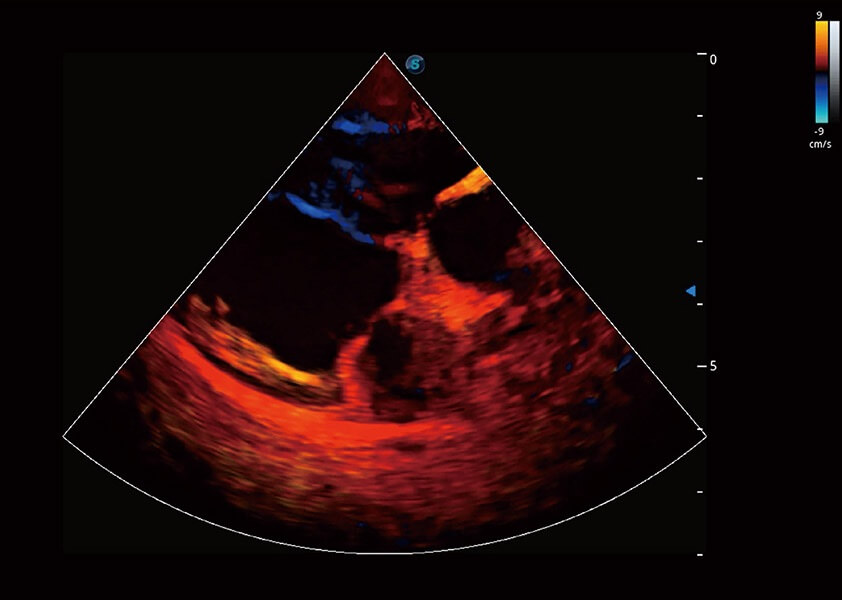

ProPet 60 作为一款高端台式动物超声设备,为动物医生的日常诊断提供了一系列贴合动物临床需求、解决临床实际问题的高级成像功能。凭借全系列高清探头,满足医生对腹部、心脏、生殖、浅表、肌骨等成像的所有需求,切实帮助您提升检查效率,提高诊断信心。